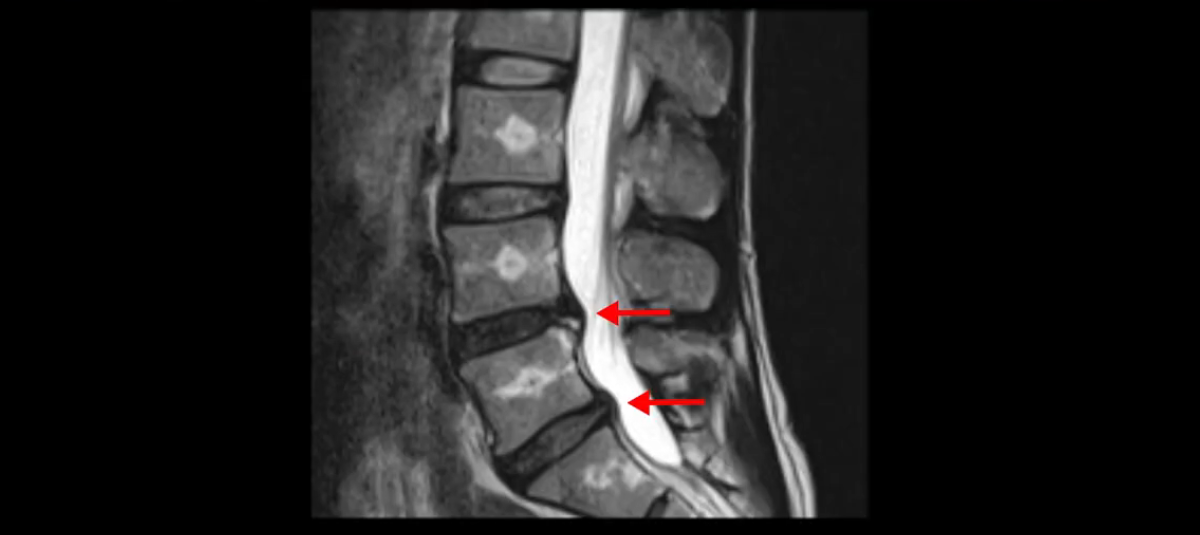

우선 이분의 MRI를 보고 먼저 설명을 드린 후 이런 환자분들의 통증의 원인은 무엇인지, 그리고 치료는 어떻게 해야 하는지 자세히 설명 드리겠습니다.

이분 MRI를 보시면 두 마디의 퇴행성디스크가 있습니다. 그리고 디스크가 조금씩 밀려 나와 있고요. 그런데 디스크 탈출 정도는 두 마디 다 심하지 않습니다. 4번 5번에는 디스크 탈출이 약간 있고,

척추관협착도 약간 진행이 되고 있고요.

5번 1번은 디스크 탈출이 가운데 쪽으로 살짝 있습니다.

중요한 것은 이 정도 경미한 탈출과 협착으로는 양쪽 다리가 저리고 아플 수가 없습니다.

그리고 만약에 이 디스크가 급성으로 찢어진 것이라면 아주 심한 디스크성 통증이 있겠죠. 기침이나 재채기를 하면 심하게 아프고 허리를 조금만 구부려도 아주 날카로운 통증들이 생길 겁니다. 그런데 이분은 이런 증상이 전혀 아닙니다. 디스크의 돌출 정도와 협착이 전혀 심하지 않기 때문에 이분이 가지고 계신 양쪽 다리 저림, 특히 이분은 누워있을 때도 양쪽 다리가 저리다고 하는데, 디스크 때문에 그런 증상은 생길 수가 없습니다. 또 이 디스크는 오래된 디스크, 이미 찢어진 섬유륜이 아문 디스크이고, 그러니까 이분은 기침이나 재채기를 못하는 증상이 없는 거죠. 그 다음에 허리를 구부릴 때 뻐근한 증상은 있지만 아주 날카로운 통증은 없습니다.

이분 MRI를 보시면 퇴행성디스크가 있고 약간의 협착이 있지만 이 정도의 퇴행성디스크와 협착으로는 신경이 눌려서 양쪽 다리가 저리고 아픈 증상이 나올 수가 없습니다. 그래서 MRI와 이 환자분의 다리 증상이 매치가 안 된다고 하는 의사들이 많은 겁니다.